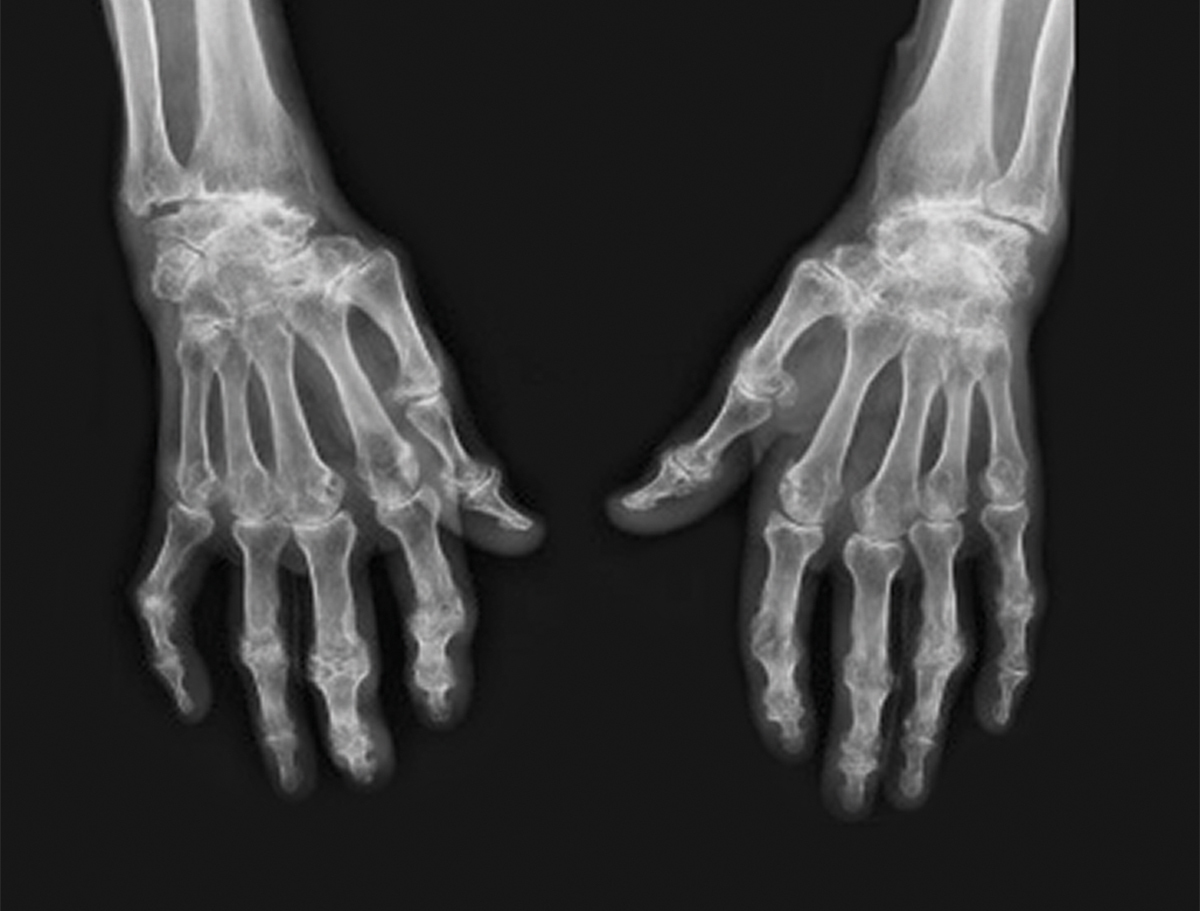

Quel est votre diagnostic ?

Il s'agit de l'aspect radiologique d'une polyarthrite rhumatoïde. Cette patiente a une polyarthrite rhumatoïde érosive très évoluée : carpite fusionnante des deux poignets, érosions bilatérales de la styloïde cubitale, arthrite radio-ulnaire distale gauche, érosion des têtes métacarpiennes des 1er et 2e rayons de la main gauche ainsi que des 1er, 2e et 3e rayons de la main droite, pincement des interlignes interphalangiens proximaux aux deux mains réalisant de véritables ankyloses au niveau des 2e et 3e rayons de la main gauche.